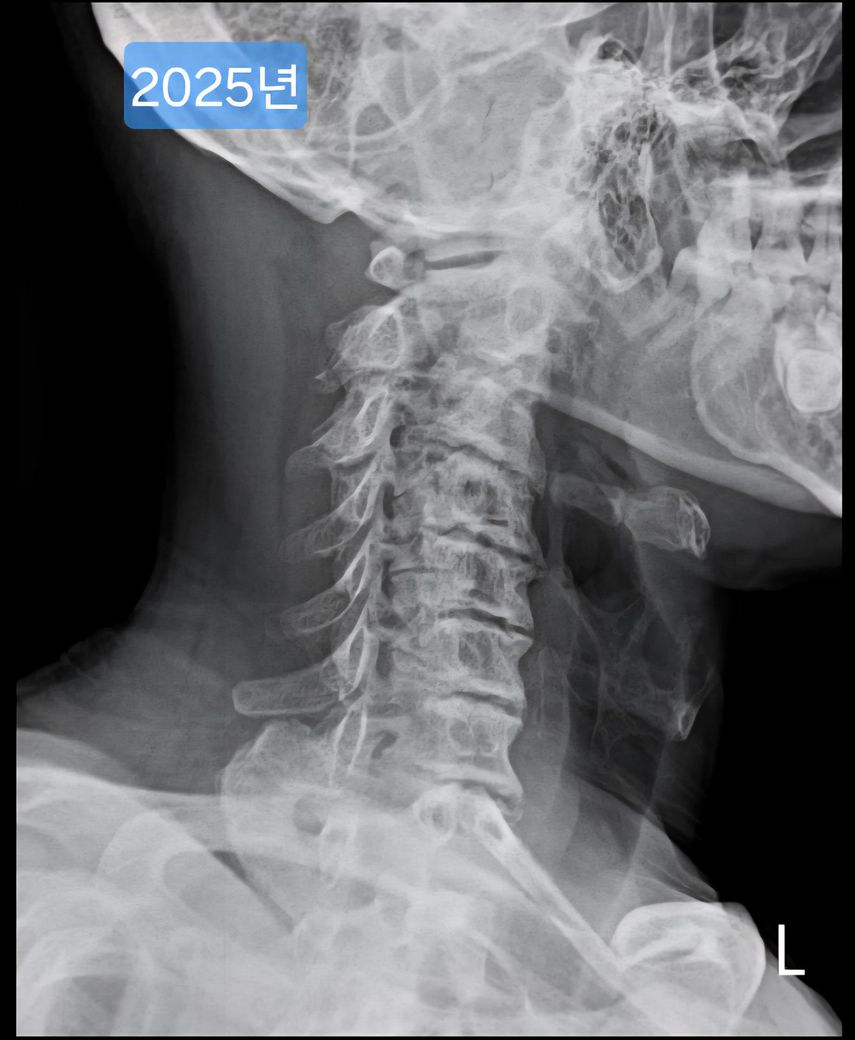

목이 일자목, 경추사이 공간 좁음 등 형태가 안 좋은데요.

여러 방도로 제 목 엑스레이 사진을 보여드리면

현재 목의 형태가 안 좋은건 충분히 알겠는데.